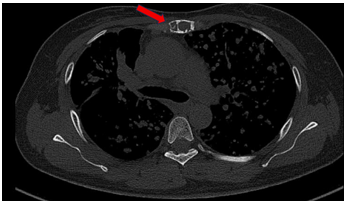

Bệnh nhân đi khám tại bệnh viện Bạch Mai được chụp cắt lớp vi tính lồng ngực phát hiện nhu mô thùy trên có khối đặc kích thước 40 x 35mm, các nốt đặc đường kính <12mm lan tỏa nhu mô hai phổi, ổ tiêu xương ức kích thước 31 x 13mm.

Hình 1: Hình ảnh tổn thương phổi trước điều trị: nhu mô thùy trên có khối đặc kích thước 40 x 35mm (mũi tên màu đỏ), các nốt đặc đường kính <12mm lan tỏa nhu mô hai phổi (mũi tên màu xanh)

Hình 2: Hình ảnh tổn thương xương trước điều trị: ổ tiêu xương ức kích thước 31 x 13 mm (mũi tên màu đỏ)